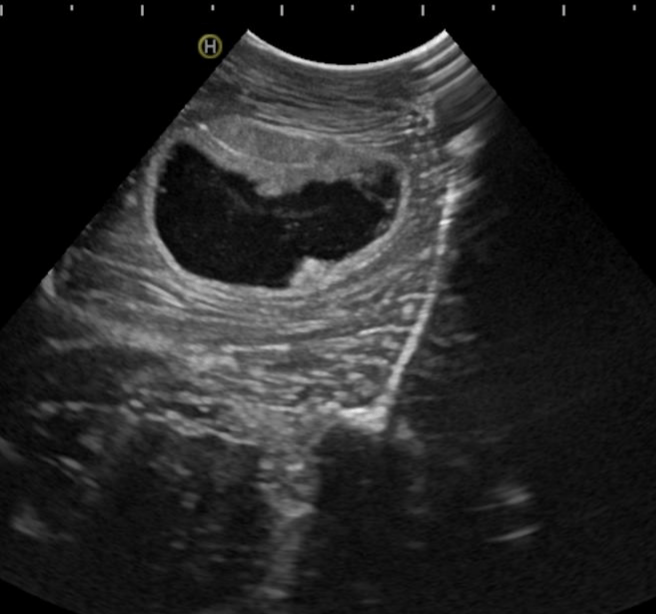

The project aims to analyze intraoperative ultrasound images of glioblastomas and develop new prediction survival models through advanced neuroimaging processing techniques and machine learning algorithms. To collect data, we promoted the creation of the first international database of intraoperative ultrasound images of brain tumors (BraTioUS-DB), in which we will collaborate with at least 6 other hospitals. At the moment we are awaiting the IRB approval of the participating centers, being the first to obtain it the Fondazione Istituto Neurologico Carlo Besta, Milano, Italy. https://www.istituto-besta.it/neurochirurgia

Predicting the survival of patients diagnosed with glioblastoma (GBM) is essential to guide surgical strategies and subsequent adjuvant therapies. Intraoperative ultrasound (ioUS) is a low-cost, versatile technique available in most neurosurgical departments. The images from ioUS contain biological information possibly correlated with the tumor's behavior, aggressiveness, and oncological outcomes. Today's advanced image processing techniques require a large amount of data. Therefore, we propose creating an international database aimed at sharing intraoperative ultrasound images of brain tumors. The acquired data must be processed to extract radiomic or texture characteristics from ioUS images. The rationale is that ultrasound images contain much more information than the human eye can process. Our main objective was to identify a relationship between these imaging characteristics and overall survival (OS) in GBM. The predictive models elaborated from this imaging technique will complement those already based on other sources, such as MRI and genetic and molecular analysis. Predicting survival using an intraoperative imaging technique that is affordable for most hospitals would greatly benefit patient management.